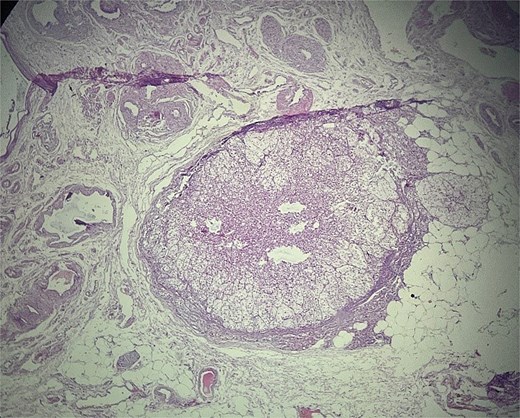

Microscopic evaluation (hematoxylin and eosin) demonstrated an endometrial polyp without atypia, multiple leiomyomas, and bilateral benign serous cystadenomas. Sections from the left fallopian tube and adjacent mesosalpinx revealed a small, well-circumscribed nodule (~3 mm) within the mesosalpinx (Figs 1–3). The nodule was composed of bland polygonal cells with distinct borders and clear to finely granular eosinophilic cytoplasm. Nuclei were round to oval, centrally located, and uniform, without pleomorphism, hyperchromasia, necrosis, or increased mitotic activity. The cells were arranged in nested/trabecular architecture resembling zona fasciculata; no medullary component was identified. These features supported the diagnosis of ectopic adrenal cortical tissue.

Ectopic adrenal cortical tissue in the mesosalpinx, forming a well-circumscribed nodule without invasive features. H&E stain, ×40.